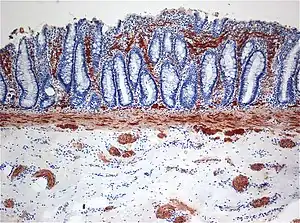

| Histopathology of Hirschsprung disease showing abnormal acetylcholine esterase (AchE)-positive nerve fibers (brown) in the mucosa | |